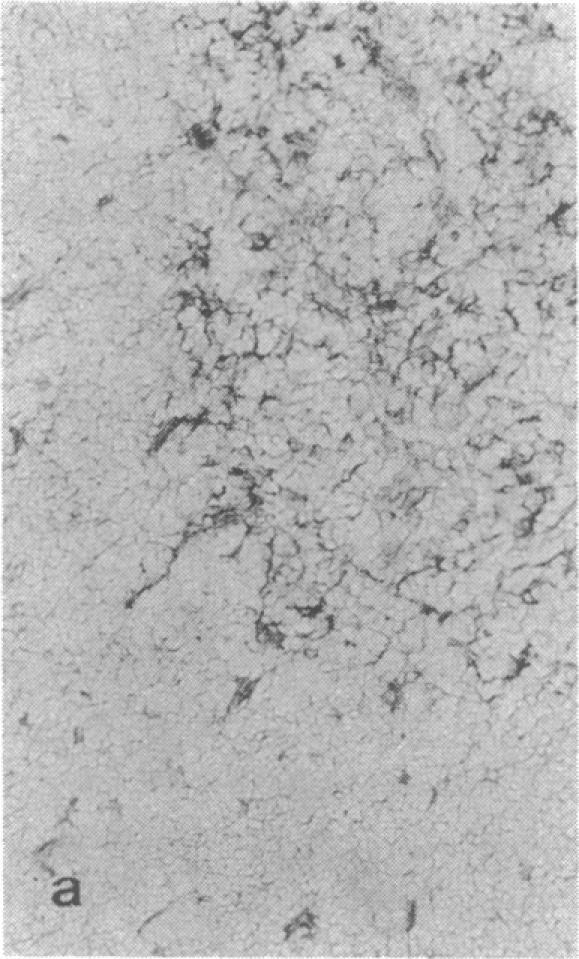

Thymic epithelial cells (TECs), the major component of the thymic microenvironment, can be modulated by pituitary hormones. We have shown previously that prolactin (PRL) can influence the endocrine activity of TECs and stimulate TEC proliferation as well as cytokeratin expression, suggesting the existence of PRL receptors on TECs. Using a series of monoclonal antibodies (mAbs) to the extracellular domain of the rat liver PRL receptor, we have demonstrate that rat TECs bear specific receptors for PRL, as assessed by immunoblotting as well as by immunocytochemistry experiments. Using a probe specific for the long form of PRL receptor, mRNAs of 6.7 and 10.1 kilobases were detected, although by immunoblot the major protein in TECs had a molecular mass of 43 kDa. Functionally, these mAbs were able to modulate thymulin secretion, as well as TEC proliferation. Moreover, the mAbs cross-reacted with human TECs and were able to mimic the action of PRL on these cells. These data bring further support for the general concept of the neuroendocrine immune circuit and extend the notion for a pleiotropic role of PRL as an immunomodulatory hormone.